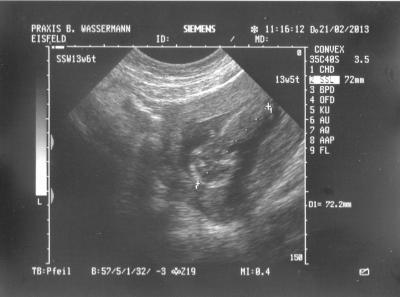

hatte jetzt endlich den 2 termin :) und musste natürlich ein zusätzlichen us machen lassen muss ja das krümmelchen sehen aber leider nicht so deutlich zu sehen wie beim ersten mal aber bin erstmal glücklich das alles i.o. war und der krümmel schön gewachsen ist von kopf bis st. 7,2 cm lang in der 9 ssw waren es noch 2,7 cm so und morgen kommt dann die 14 ssw und hier das neue bildchen unten links kop und dann stück bauch + rücken :)

Bild zu FA termin von heute morgen - Forum für August - Mamis